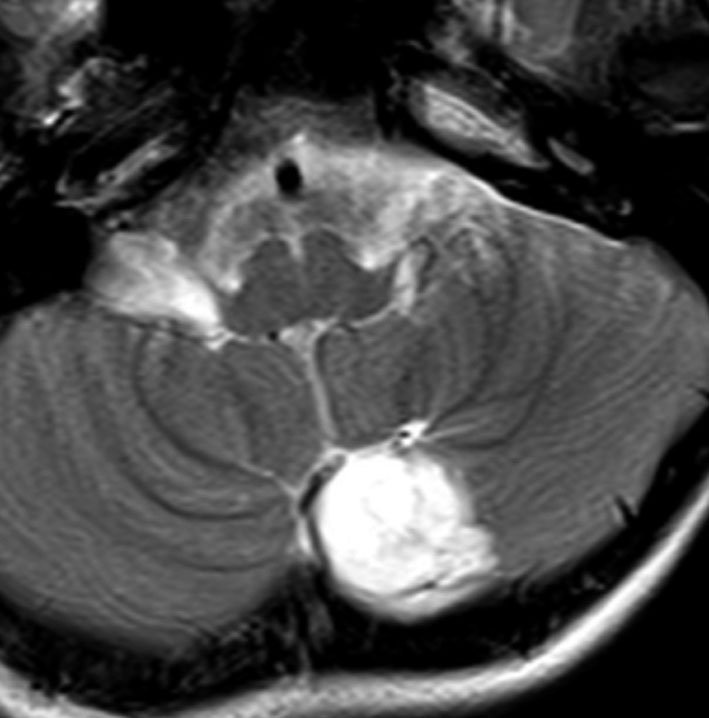

小脳類皮のう胞

偶然発見された女の子のものです。左のCTで石灰化があります。右の拡散強調画像 DWI で白く高信号に描出されるのが特徴です。手術では腫瘍内部に毛髪がたくさんありました。後下小脳動脈に強く癒着していて,脳軟膜からの剥離もできませんでしたが,完全摘出しました。無症状でも”完全”摘出 complete removal するべきです。